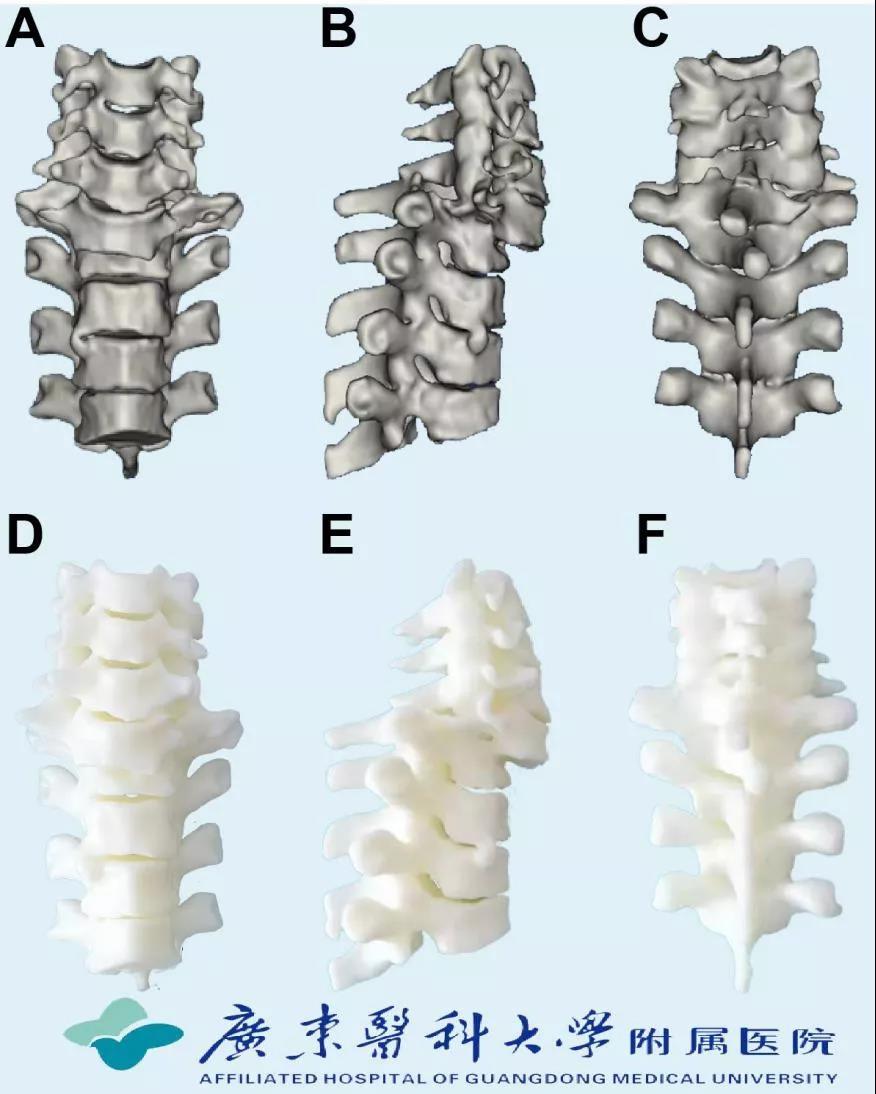

脊柱微创外科主任魏波,副主任孙欣,彭智恒、黄维渊博士,郑锦畅副主任医师,黄成硕主治医师,梁振医师通过3D技术重建患者颈椎序列(如图2所示),全面研究骨折及脱位情况,充分讨论患者病情,分析手术难点,最后设计出“前-后-前”联合的颈椎椎体脱位复位固定方案。

图2、3D技术重建患者脱位颈椎序列